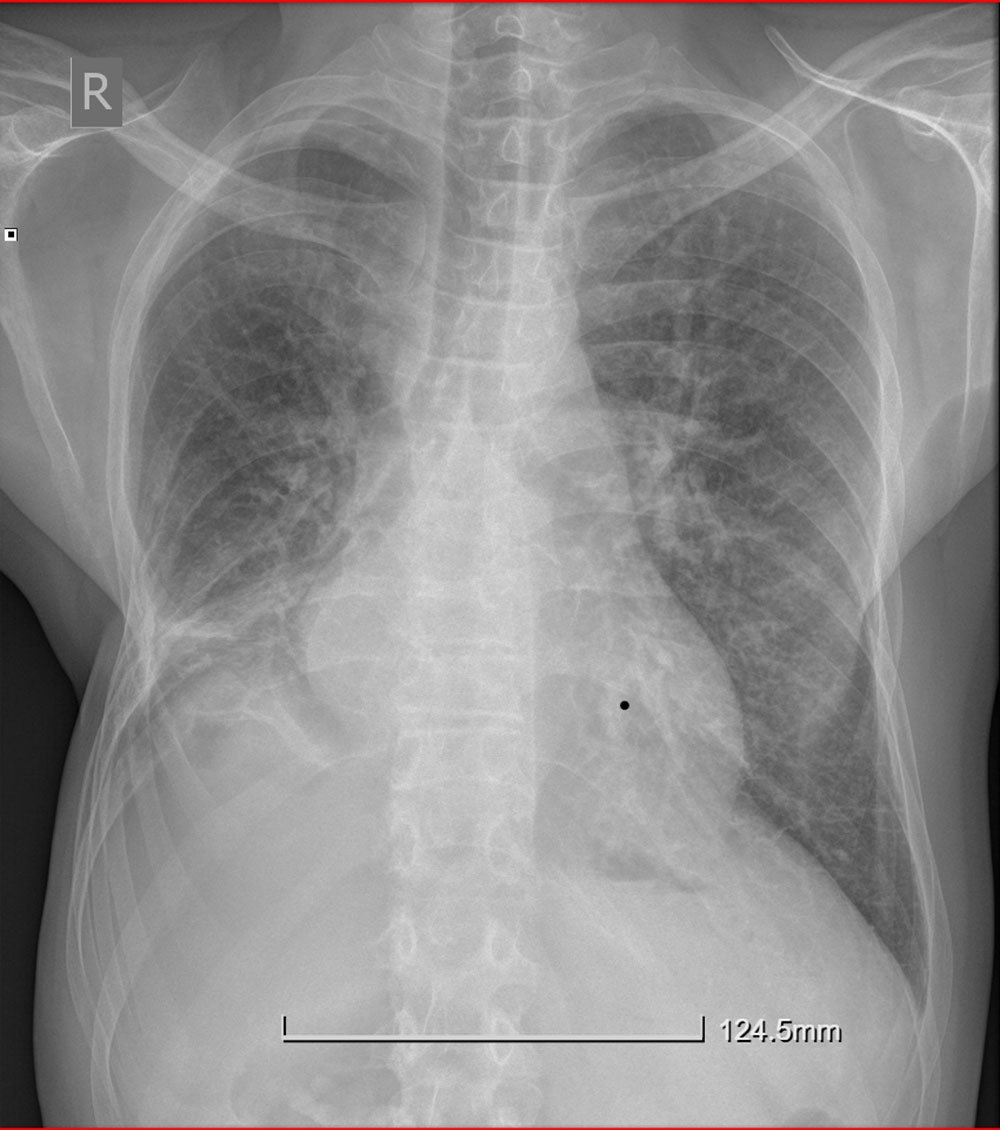

CRX